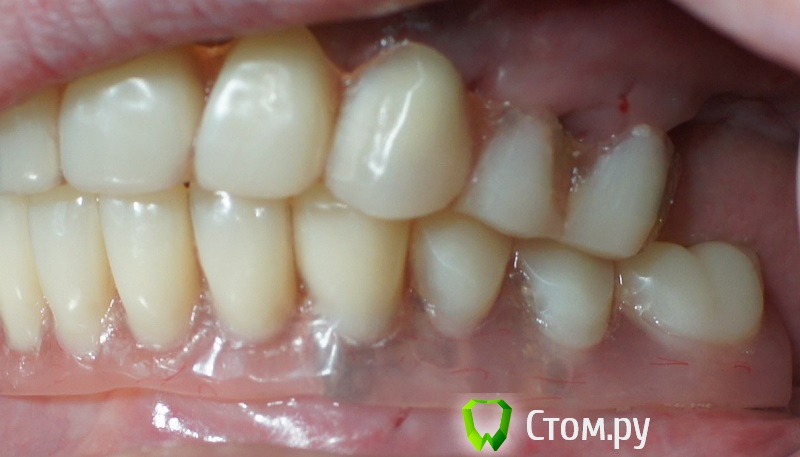

rin3225 Опубликовано 8 октября, 2014 Поделиться Опубликовано 8 октября, 2014 У пациента было желание сделать красивые зубы и улыбку!Проблема заключалась в массивной верхней челюсти , глубоком перекрытии и пациент не мог уйти без зубов! Отлив модели и выставив в центральную окклюзию было понятно, что без удаления всех зубов и поднятия прикуса с данной проблемой вопрос не решится. Обговорив все нюансы с пациентом,и получив согласие, было запланировано. заранее изготовлены акриловые протезы, предложено удаление всех зубов с одномоментной установкой имплантатов, внутриротавая сварка для первичной стабильности имплантатов и немедленная нагрузка 16 Ссылка на комментарий

rin3225 Опубликовано 8 октября, 2014 Автор Поделиться Опубликовано 8 октября, 2014 Видел… Видел…У этих людей тоже нарушение в концепции?Я не собирался повторять то о чем Вы говорите! Просто сделана первичная стабильность имплантов с немедленной нагрузкой, в дальнейшем это будет несьемная конструкция с цементной фиксацией. Балка не служит опорой для протеза и в дальнейшем будет убрана. Ссылка на комментарий

ILGAMSA Опубликовано 8 октября, 2014 Поделиться Опубликовано 8 октября, 2014 А я бы фронт внизу оставил. Работу только сделана?Тогда ждем фото и Рентгены через полгода, год. 5 Ссылка на комментарий